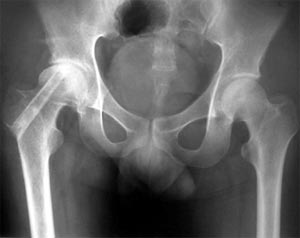

MRI显示股骨头坏死

患者35岁,双侧股骨头坏死。将患者的骨髓细胞与具有支撑力的植骨材料复合植入骨修复区。术后3年患者髋关节功能良好,无塌陷,无疼痛。